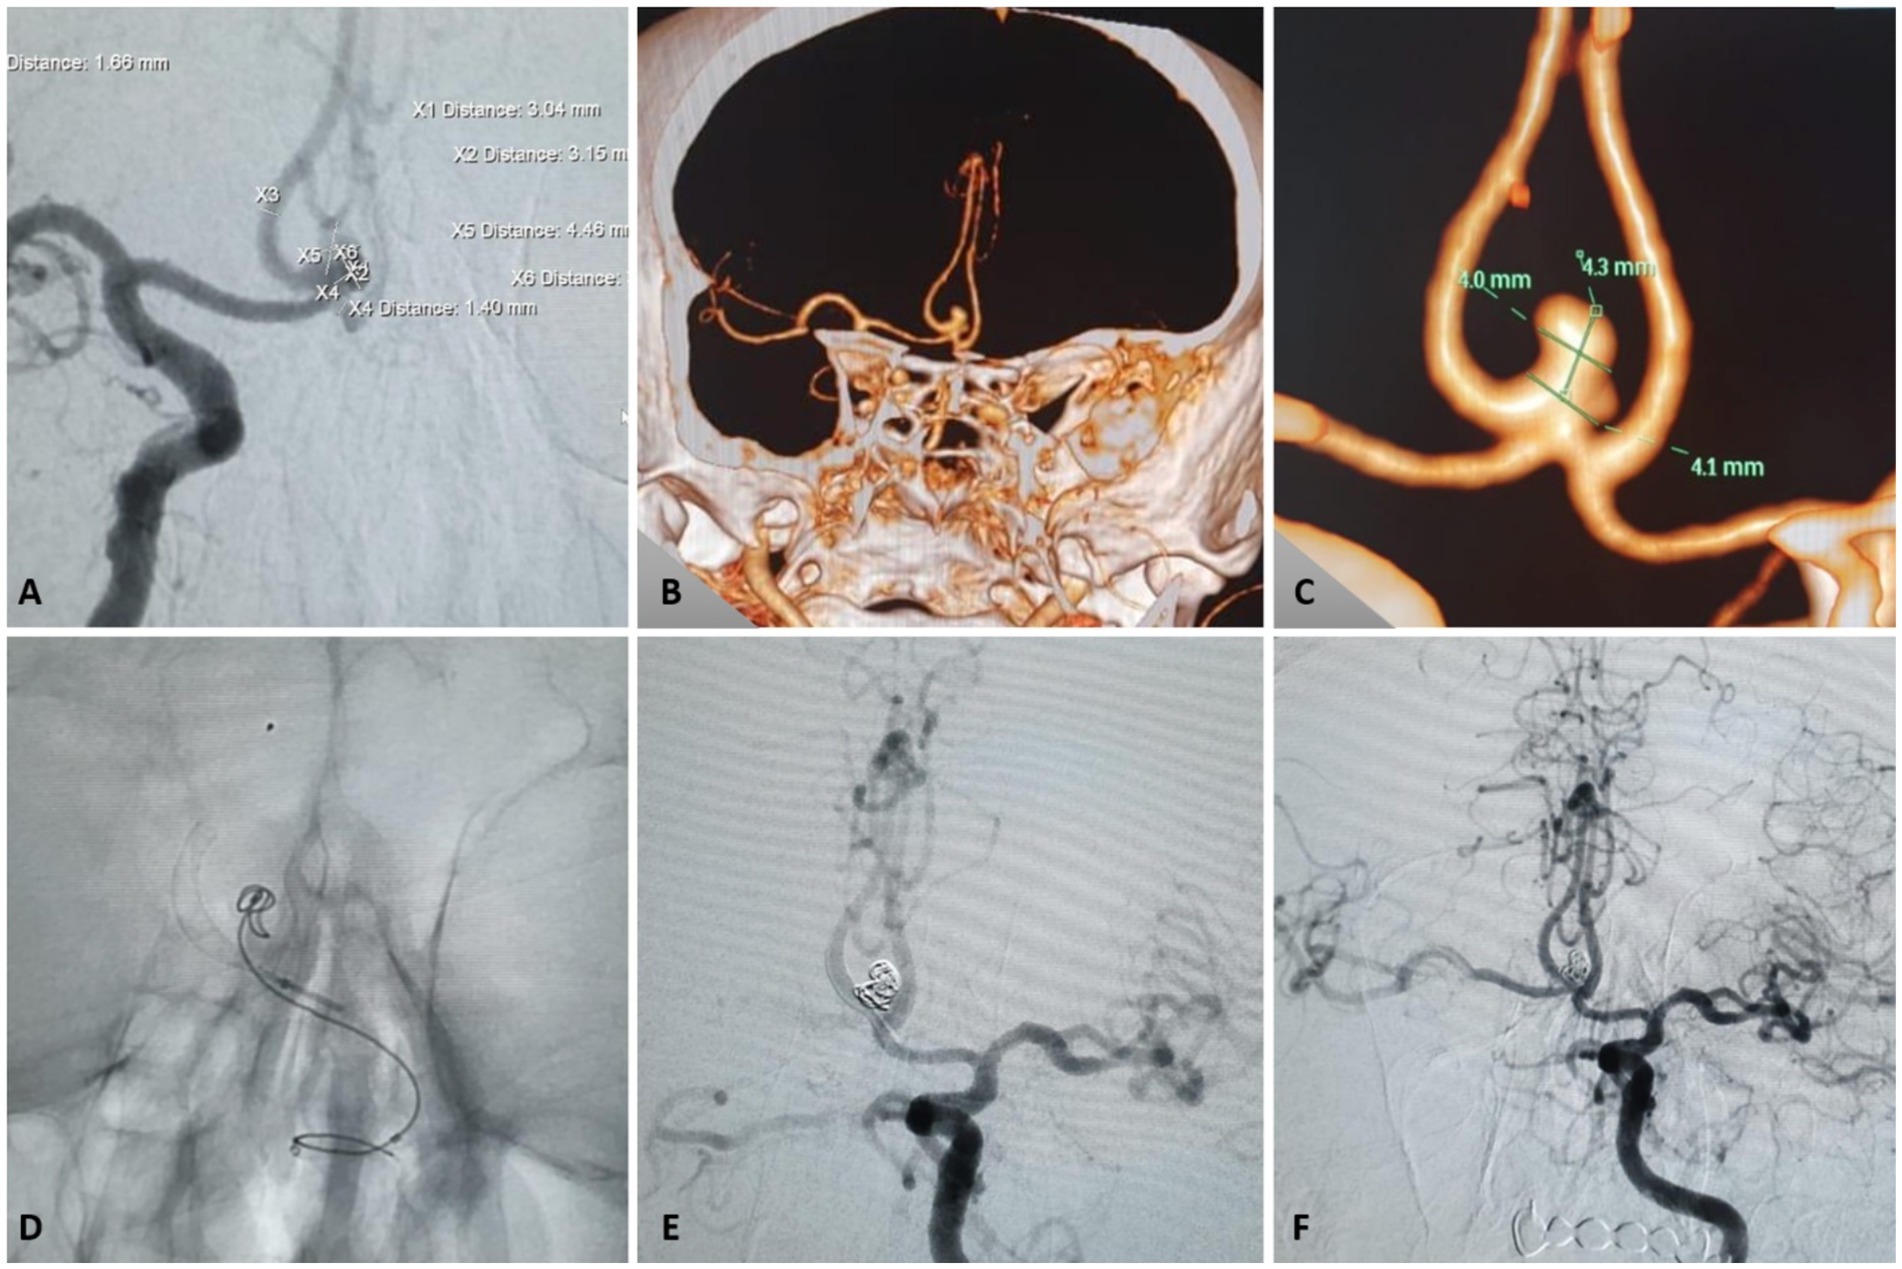

Figure 3

Clinical case illustrating a negative Kazakh ThromboTest (KTT) despite complete resistance on VerifyNow™ in the treatment of an anterior communicating artery (AComA) aneurysm using a P48 HPC flow diverter. (A) Frontal angiographic view showing a 4.4 × 4.0 × 3.1 cm AComA aneurysm. (B,C) Corresponding CT angiography images. (D,E) Intraoperative application of the KTT technique. (F) Successful deployment of the FRED device with no thrombotic complications.